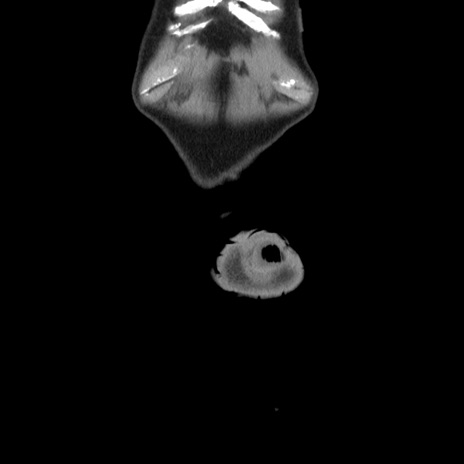

横断像